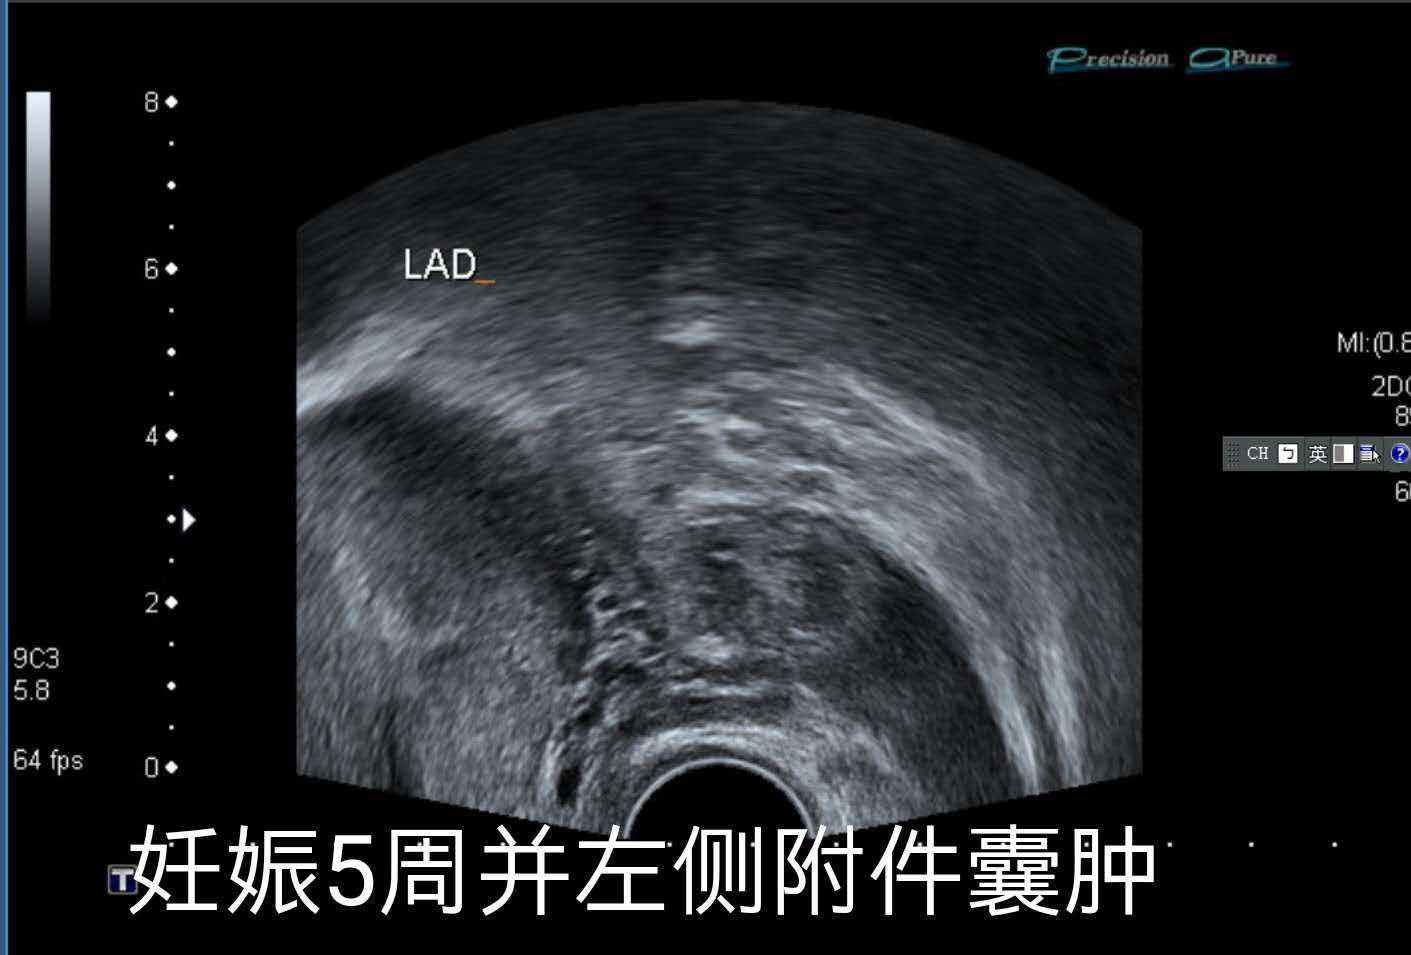

2019年3月5日的B超。

2019年3月5日,小兰再次来到佛教医院复查,医生给她查了阴道B超检查,确认了她怀有宫内活胎。

腹腔内的少量腹水。

发现宫内活胎的同时,医生还发现了小兰腹腔内有少量腹水。

同时,医生还发现了小兰的左侧附件有个囊肿。由于小兰两年前就有左侧附件的崎胎瘤,目前小兰也没有什么特别不舒服,因此,医生没有对小兰做特别的处理。